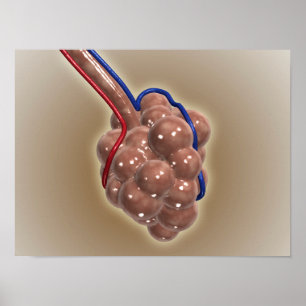

Poster Gros Plan D'Alveolus

Prix30,15 $CA